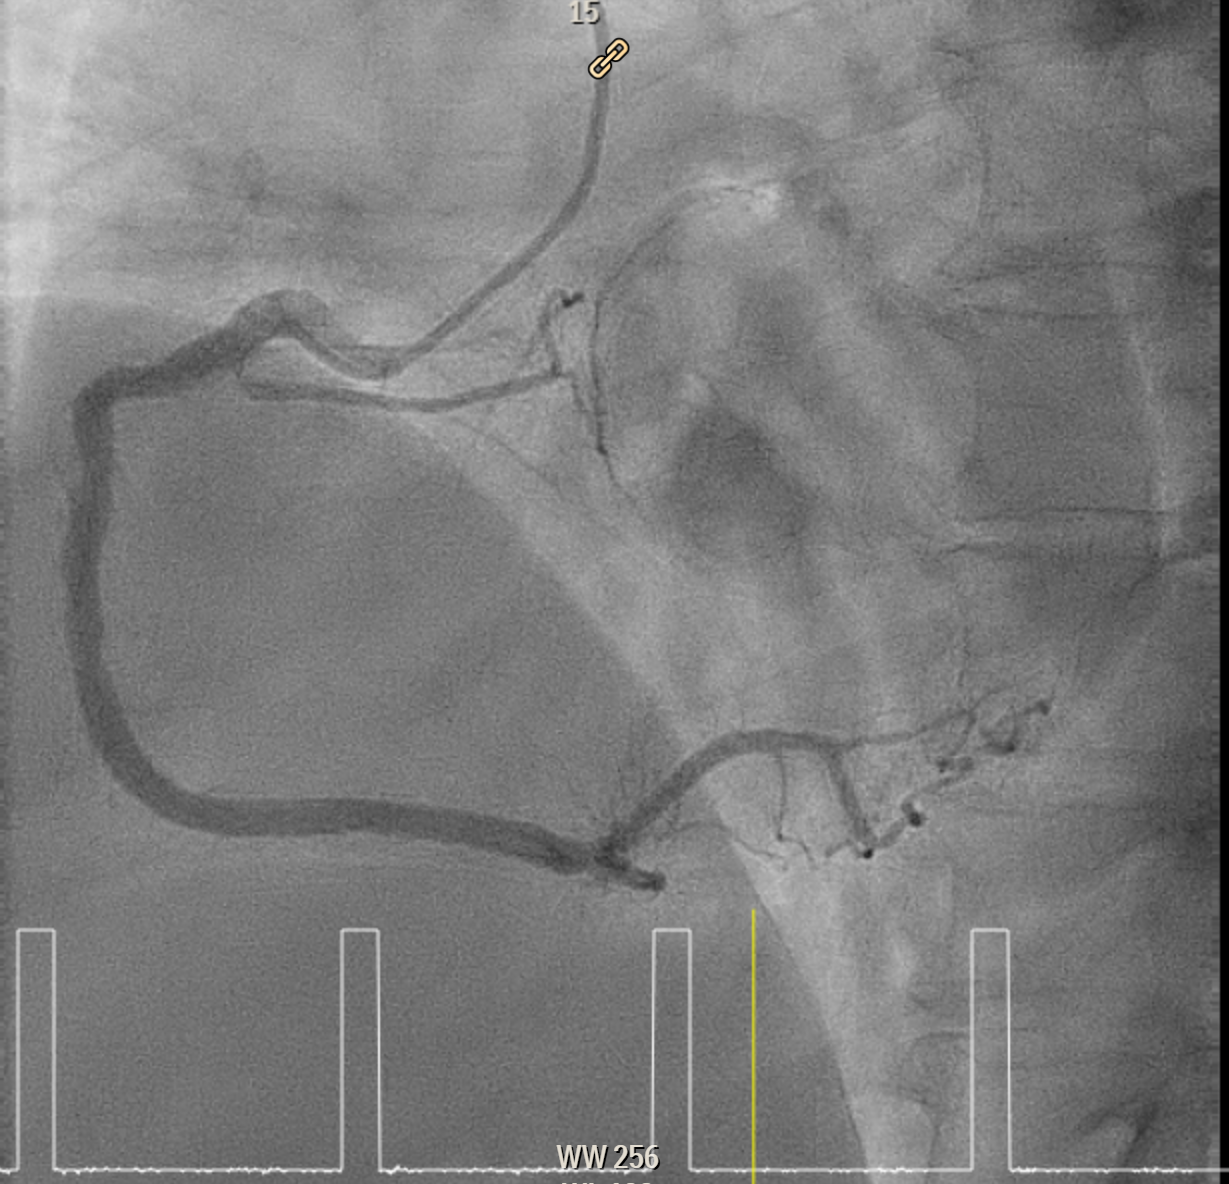

Elective angiogram was performed 3 months later as he declined procedure during index admission. Coronary angiogram showed total occlusion of proximal LAD at bifurcation of first diagonal and first septal branches. It received collateral supply from conus branch and first septal branch (Rentrop 2). J-CTO score was 2, and PROGRESS-CTO score was 1, indicate moderate complexity. Additionally, RCA was huge and dominant, while proximal first OM branch of LCX was 80–90% diseased.